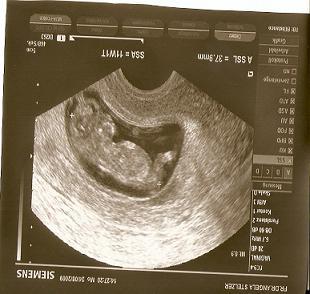

huhu ich seh da immer soooo liebe ultraschallbilder .. nun find ich das mein zwergi euer zwergi garned ähnlich schaut ich find das es nur einen rießen schädel hat und kein kinn .. oder bilde ich mir das nur ein bitte ehrliche antworten ;(

Bild zu komisch - Forum für März - Mamis